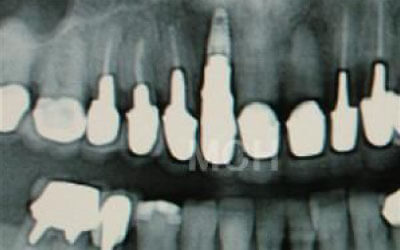

ブリッジとインプラントでは、前後の歯の寿命に大きな違いがあります。ブリッジでは、支えとなる歯を虫歯がなくても大きく削る必要があり、さらに噛む力が通常の1.5倍かかるため、その寿命が短くなりがちです。実際の統計によると、ブリッジの支えとなる歯の68%が、10年以内に抜歯を余儀なくされるという結果が出ています。

噛むとき、誰でも歯に何十キロもの力がかかっています。当然、歯の本数が減れば減るほど、残った歯にかかる負担は大きくなります。ブリッジ治療の場合、失われた歯にかかっていた力は、前後の歯で支えることになります。その結果、残った歯には、抜歯していないときに比べて1.5〜2倍程度の力がかかることになります。

入れ歯を使うと、バネをかけている歯や残っている歯への負担が大きくなります。多くの方が無意識のうちに残っている歯で噛んでしまうため、使用頻度が非常に高くなり、過剰な力が加わります。その結果、歯が折れたり、残っている歯の寿命が短くなることがあります。しかし、インプラントの場合、人工歯根を通じて骨が力を支えるため、残っている歯への負担は圧倒的に少なくなります。

ブリッジなどの治療では、前後の歯を大きく削る必要があります。場合によっては、虫歯がないのに歯の神経を取らなければならないこともあります。実際、神経を取って被せ物をすると、その歯は一気に「最終段階」に進んでしまうのです。しかし、インプラント治療では、前後の歯を削ることも、神経を取ることもありません。歯の寿命を延ばすためにも、健康な歯をできるだけ削らないことが非常に重要なのです。

歯科の統計データをご紹介します。

インプラントは、10年経っても約90~95%の確率で問題なく使い続けられています。

一方、ブリッジの場合は、10年後に残っているのは約30~35%にとどまります。

ブリッジが使えなくなる主な原因は、支えている歯が悪くなり抜歯が必要になるケースがほとんどです。